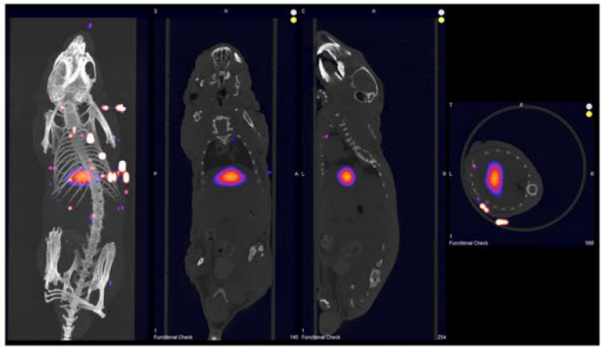

结直肠癌模型-前哨淋巴结-肿瘤成像

转铁蛋白包封的纳米粒,靶向肿瘤细胞TfR

纳米粒在经前哨淋巴结转移的肿瘤中靶向积累

并经肝、肾代谢。